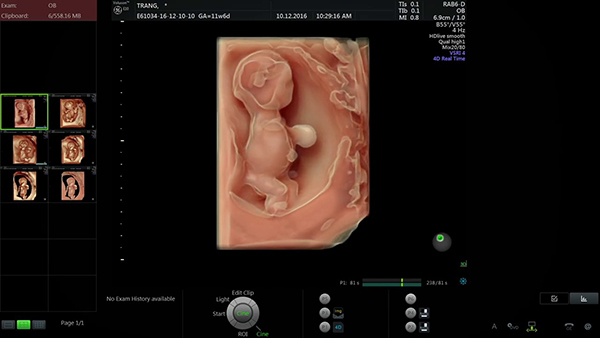

Siêu âm thai 11 tuần 6 ngày là cột mốc đặc biệt vì đây là những tuần cuối cùng của tam cá nguyệt thứ nhất. Lúc này, thai nhi bắt đầu có sự phát triển rõ ràng hơn, nhất là hệ thần kinh, những phản xạ cơ bản và tim thai. Vậy thai nhi 11 tuần 6 ngày sẽ có những thay đổi nào? Mẹ sẽ biết những thông tin gì khi siêu âm thai ở cột mốc này? Câu trả lời cho các mẹ ở những chia sẻ dưới đây!

Từ tuần 10 đến tuần 12 là khoảng thời gian thai nhi phát triển khá nhanh. Gần tuần thứ 12, thai nhi chỉ nặng khoảng gần 14gram và dài khoảng 50mm. Lúc này chân bé chưa duỗi thẳng nên chiều dài chỉ đo từ đầu đến mông. Nhịp tim của bé có thể đạt 160 nhịp/phút, vì thế siêu âm thai 11 tuần 6 ngày có thể nghe rõ nhịp tim của thai. Dù cơ thể còn khá nhỏ nhưng những cơ quan quan trọng như não, tim, gan, thận và hệ thần kinh đã ngày càng hoàn thiện.

Nhiều mẹ lo lắng rằng thai 11 tuần 6 ngày còn khá nhỏ nên không biết liệu kết quả có chính xác hay không. Tuy nhiên, mẹ không cần quá lo lắng về vấn đề này bởi hình hài thai nhi đã phát triển tương đối, thai cũng có những phản xạ đầu tiên như gập duỗi thân, duỗi chi,… Đây cũng là cột mốc siêu âm dị tật quan trọng mà mẹ cần thực hiện để xác định dị tật bẩm sinh.